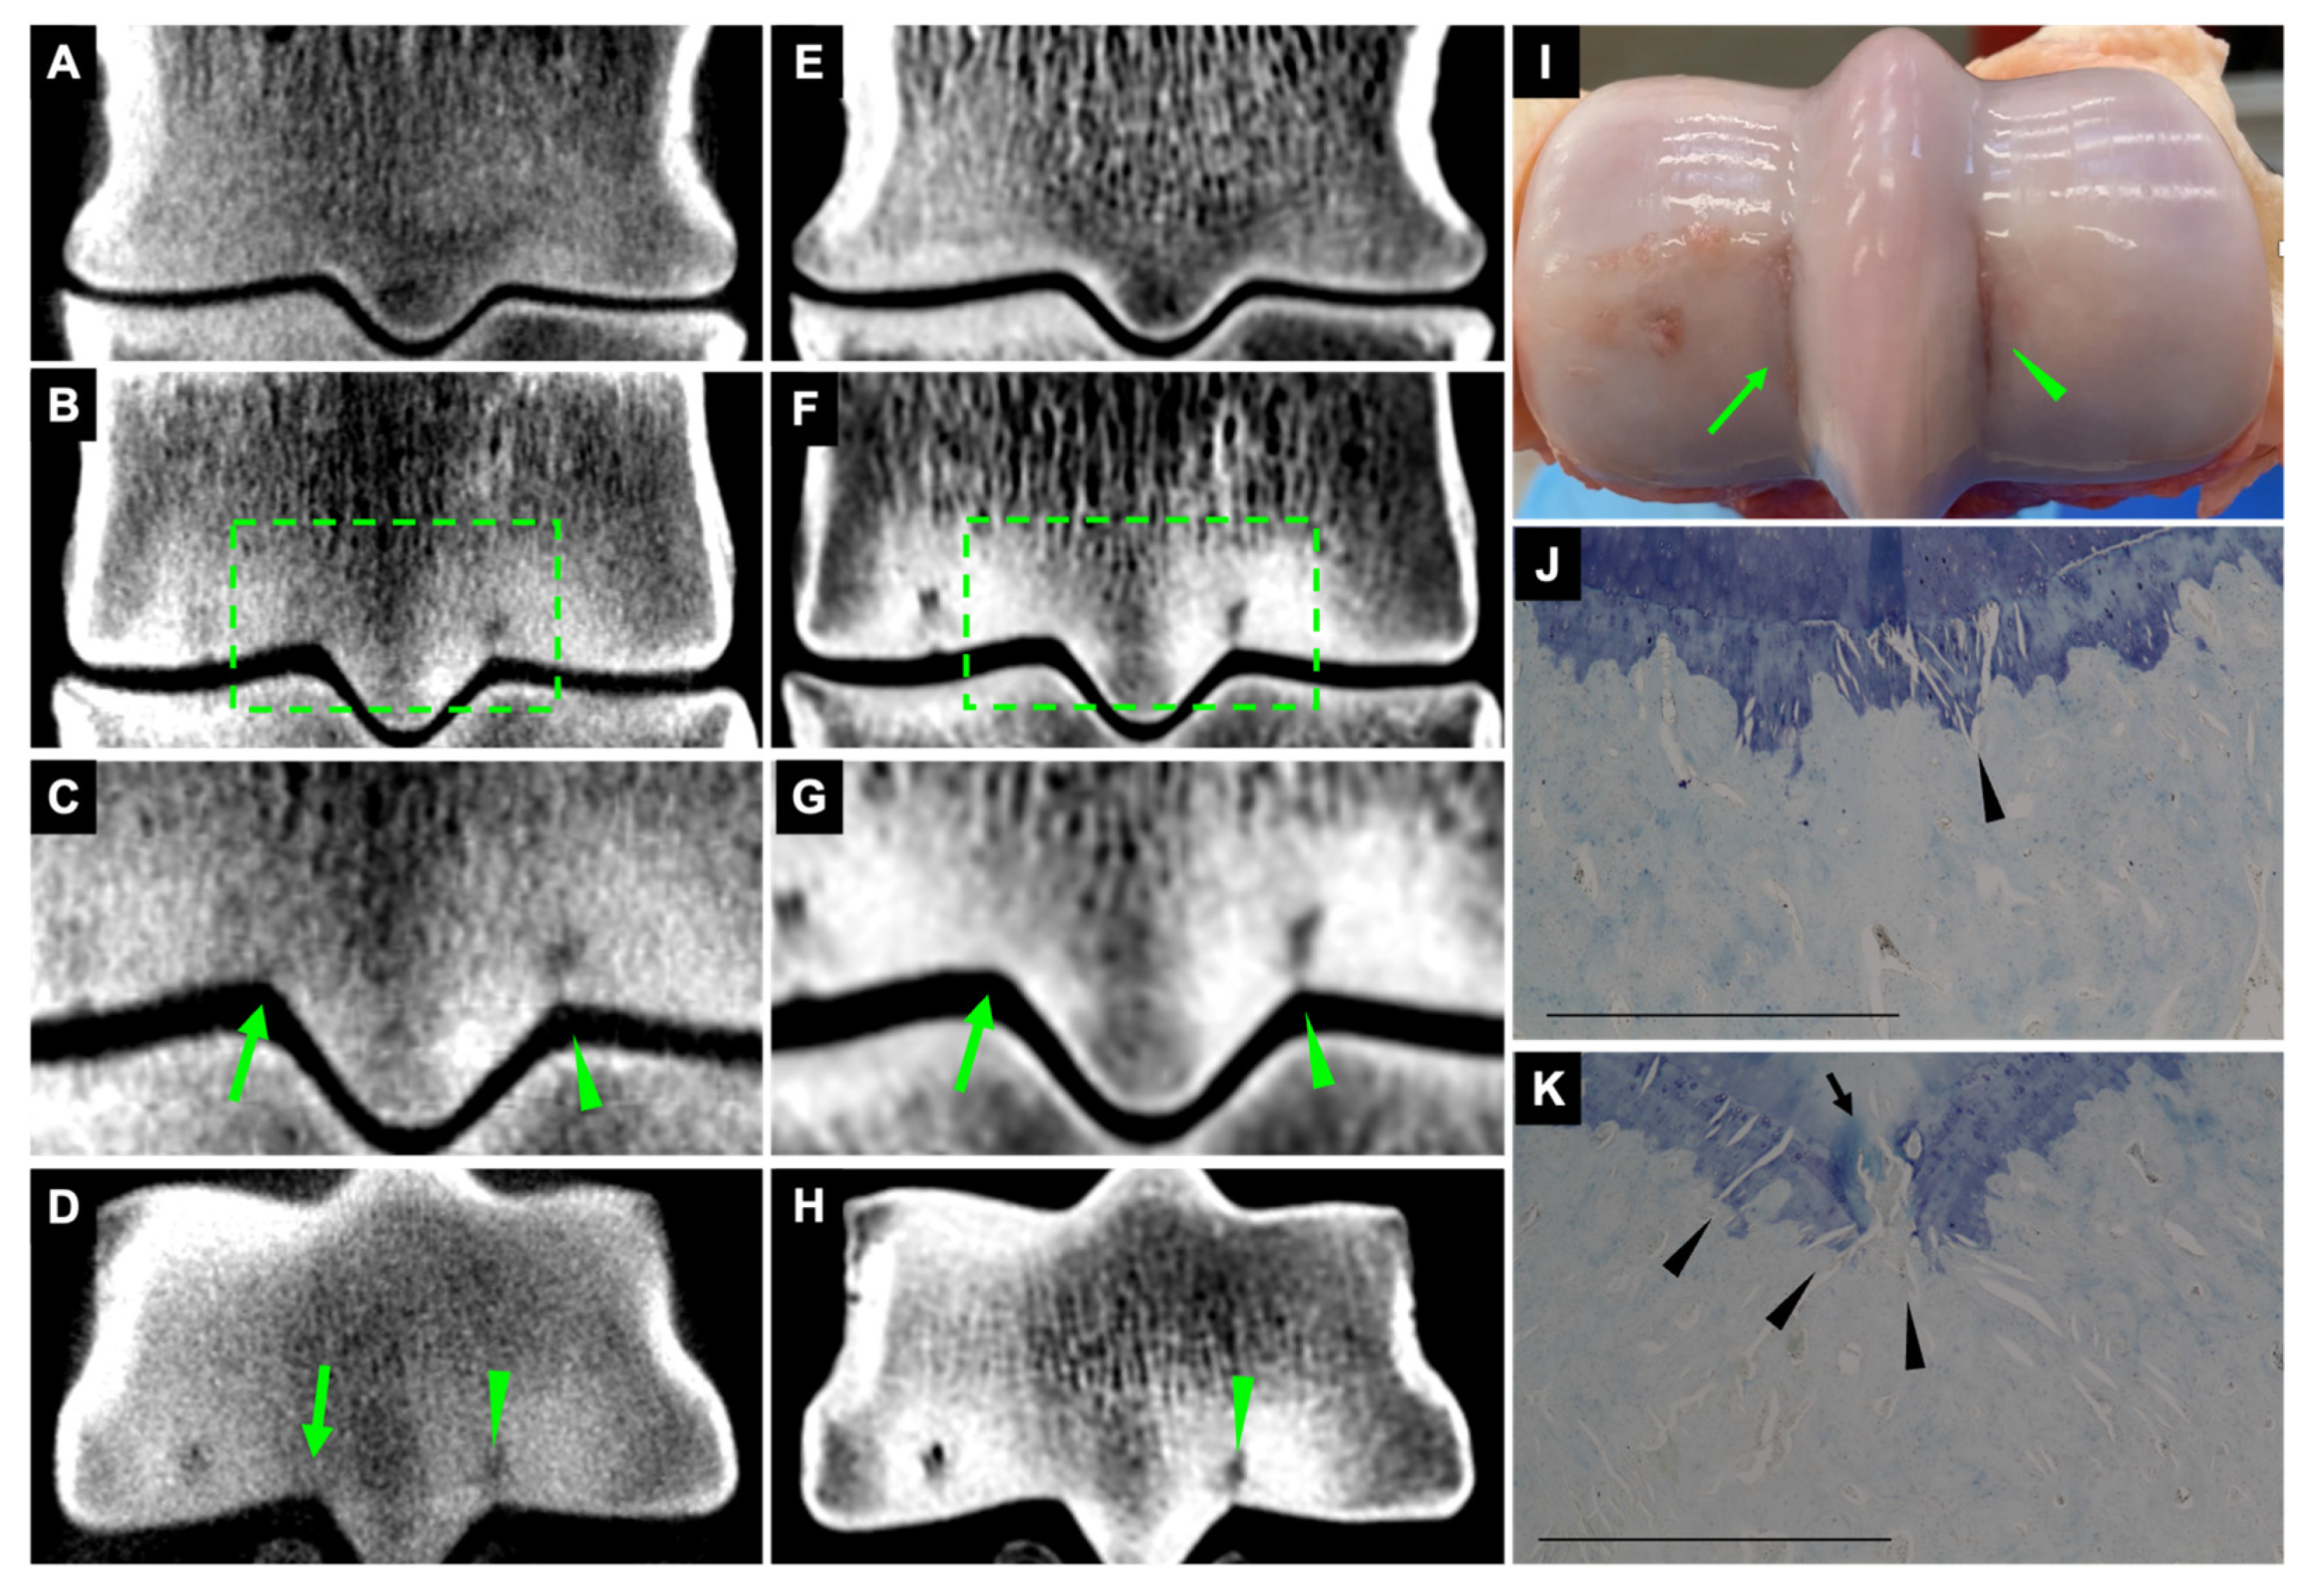

On CBCT and FBCT images, 21 fissures were identified as hypoattenuating linear defects in the subchondral bone in dorsal and transverse orientations (Figure 2).

Figure 2.

Fissures at the palmar aspect of the medial and lateral parasagittal grooves. Lateral is to the right. CBCT (A–D) and FBCT (E–H) dorsal and transverse orientation. Images (A,E) are diagrams showing the normal appearance of dorsal sections, without fissures in the parasagittal grooves. Images (C,G) are magnifications of the selected area on images (B,F). The medial parasagittal groove fissure appeared as striated hypoattenuating lines on the CBCT (arrow; (C,D)) and very subtle subchondral outline irregularity on the FBCT (arrow; (G)). The lateral parasagittal groove fissure appeared as hypoattenuating linear defects on both CBCT and FBCT (arrowhead; (C,D,G,H)). Macroscopic appearance of medial and lateral parasagittal groove fissures with articular cartilage defects ((I); arrow and arrowhead). Microscopic appearance of fissures at the medial (J) and lateral (K) parasagittal grooves. Microcracks in the calcified cartilage and subchondral bone plate appeared as oblique striated linear lesions and some were coalescing (arrowhead; (J,K)). Calcified cartilage cleft (arrow). Scale bar = 1 mm.

3.2.2. Striated Hypoattenuating Lines on CBCT and FBCT

On CBCT and FBCT images, 34 fissures were identified as subtle striated hypoattenuated lines in the subchondral bone (Figure 2 and Figure 3). The fissures were most clear on dorsal orientation and appeared as very subtle, hypoattenuating lines on transverse orientation (Figure 3).